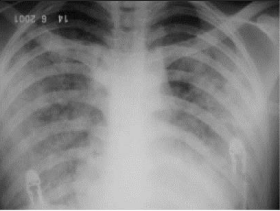

RX tórax 24 hrs após a admissão da paciente

Figura 2 - Radiografia de tórax 24 horas após internação mostrando maior confluência das consolidações